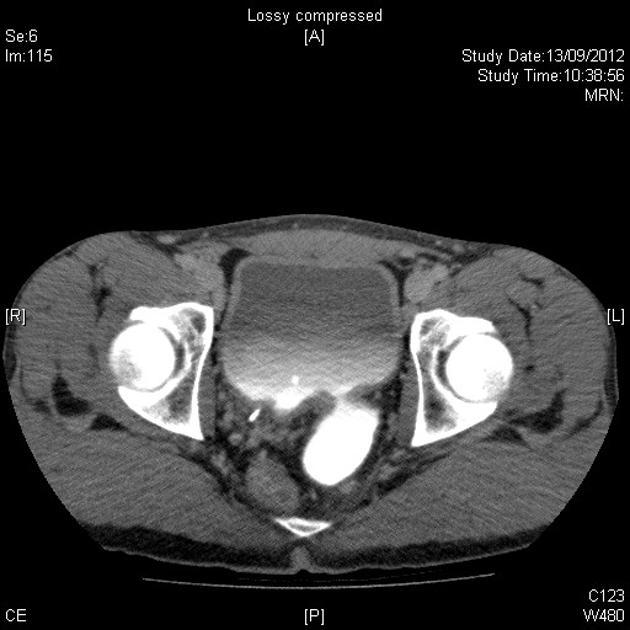

25 year old male. This is adjacent to but separate from the UVJ. Diagnosis?

Differential?

Hutch diverticulum. A congenital diverticulum, typically arising adjacent to the UVJ. Can cause recurrent UTI, vesicoureteric reflux. Wall made up of all 3 layers of bladder.

VS

Acquired bladder diverticula. Any location. Typically thinner wall- made up of prolapsed mucosa only. 2/2 obstruction, neurogenic bladder.

Urachal diverticulum. At the apex of the bladder, due to patent urachal remnant. 3 layers.